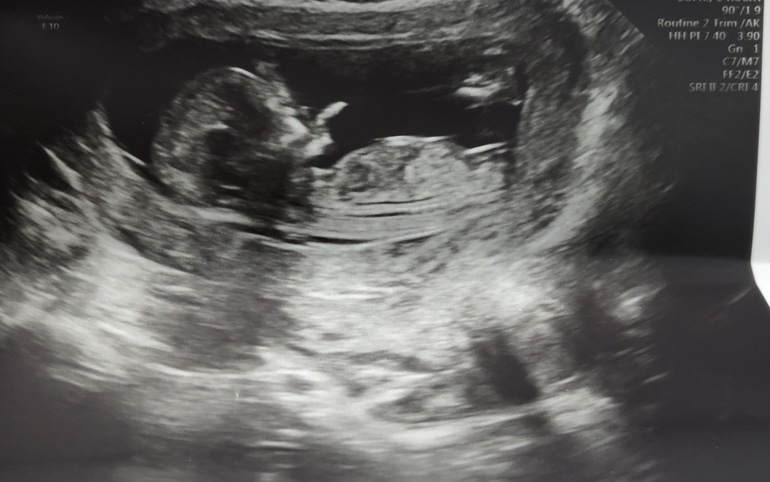

Девочка или мальчик? 13.1 нед

На фото не очень понятно. Но, по моему фото посмотрите,там тоже бугорок вдоль туловища, нам дали 100% гарантию , что девочка) врач сказала, что так выглядят половые губы в разрезе, а у мальчиков вверх торчит.

Думаю девочка, бугорок параллельно.

А бугорок - это более яркая параллельная позвоночнику черточка, верно?

Да, беленьким выделена